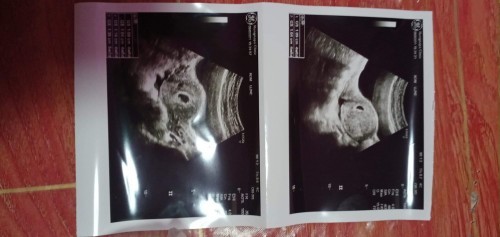

คือไปอัตซาวครั้งแรก หมอบอกว่า 5 สัปดาห์ แต่ไม่เห็นตัวเด็ก

มีใครเคยเป็นแบบนี้บ้างคะ แล้วไปอีกทีจะเห็นเด็กไหมคะ กังวลมาก#ขอคำแนะนำหน่อยค่ะ #ท้องแรกคะ #ขอบคุณสำหรับคำตอบค่ะ

บ้านนี้ตอนซาวน์ก้อ 5w 2d ค่ะ เห็นเหมือนถุงเต้นตุ้บๆ ยังไม่เห็นตัวน้องเหมือนกัน พอรอบใหม่ไปซาวน์ 9w ก็เห็นแล้วค่ะ อย่าเพิ่งกังวลไปนะคะ หมอบอกว่าส่วนมากจะเริ่มเห็นน้องตอน 5w 5d ขึ้นไป คุณแม่ใจเย็นๆก่อนน้า

ตอน5วีคเห็นแค่ถุงการตั้งครรภ์เหมือนกันค่ะ หมอจะบอกแค่ว่าฝังตัวในมดลูกหรือไม่ของเราจะเห็นถุงไข่แดงรางๆด้วยและอีก2สัปดาห์หมอนัดมาซาวด์ใหม่

5สัปดา2วันไม่เห็นอะไรเลยหมอนัดชาว2สัปดาเจอทั้งหมดถุงตั้งครร ตัวเด็ก หัวใจ พอเครื่องคำนวนอายุครรได้ปรากฏว่าอายุครร6สัปดา2วัน